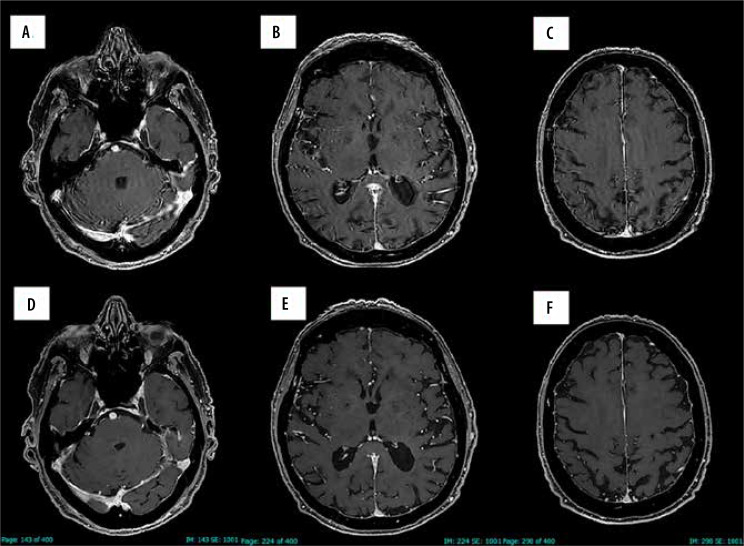

Magnetic resonance imaging (MRI) is a powerful imaging modality, but one of its drawbacks is its relatively long scanning time to acquire high-resolution images. Reducing the scanning time has become a critical area of focus in MRI, aiming to enhance patient comfort, reduce motion artifacts, and increase MRI throughput. In the past 5 years, artificial intelligence (AI)-based algorithms, particularly deep learning models, have been developed to reconstruct high-resolution images from significantly fewer data points. These new techniques significantly enhance MRI efficiency, improve patient comfort and lower patient motion artifacts. Improving MRI throughput with lower scanning duration increases accessibility, potentially reducing the need for additional MRI machines and associated costs. Several fields can benefit from shortened protocols, especially for routine exams. In oncologic imaging, faster MRI scans can facilitate more regular monitoring of cancer patients. In patients suffering from neurological disorders, rapid brain imaging can aid in the quick assessment of conditions like stroke, multiple sclerosis, and epilepsy, improving patient outcomes. In chronic inflammatory disease, faster imaging may help in reducing the interval between imaging to better check therapy outcomes. Additionally, reducing scanning time could effectively help MRI to play a role in emergency medicine and acute conditions such as trauma or acute ischaemic stroke. The purpose of this paper is to describe and discuss the advantages and disadvantages of introducing deep learning reconstruction techniques to reduce MRI scanning times in clinical practice.